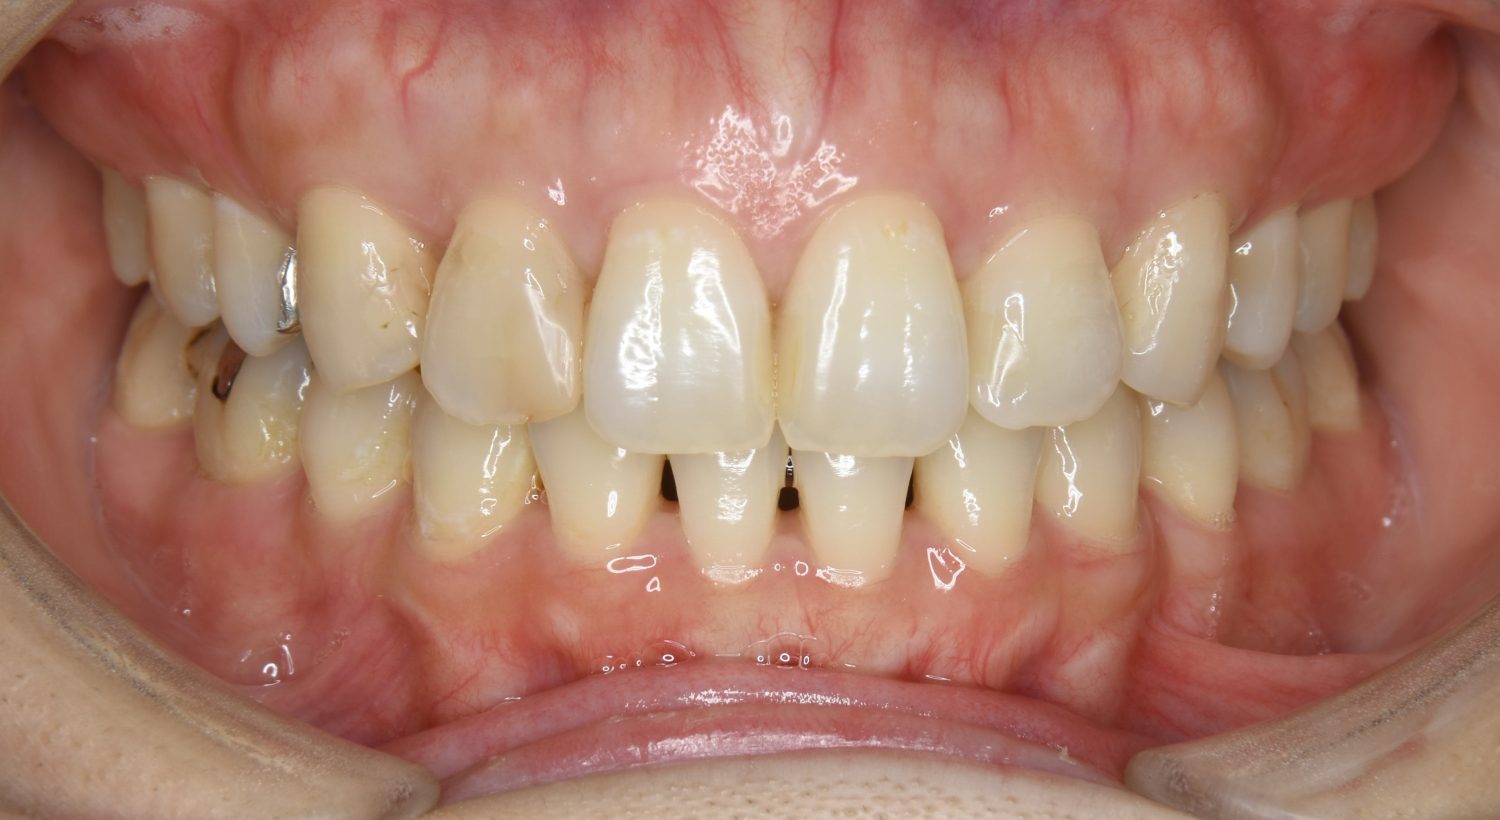

前歯部開咬の症例紹介①

Before

After

主訴

前歯が開いているのが気になる。

治療内容

上リンガルブラケット(舌側装置)、下ラビアルブラケット(唇側装置)に矯正用アンカースクリューを併用し非抜歯で治療を行いました。

治療費

1,200,000 円(税込)

治療期間

33ヶ月

通院回数

34回

想定されたリスク

※歯根吸収、歯肉退縮、歯髄壊死、顎関節症状

丸山和宏先生

ピーススマイル矯正歯科

上下の前歯が開いており前歯では全く噛めていない状態でした。臼歯の圧下を行うことで前歯でも咬合できるようになり機能面のみでなく審美面も著しく改善しました。